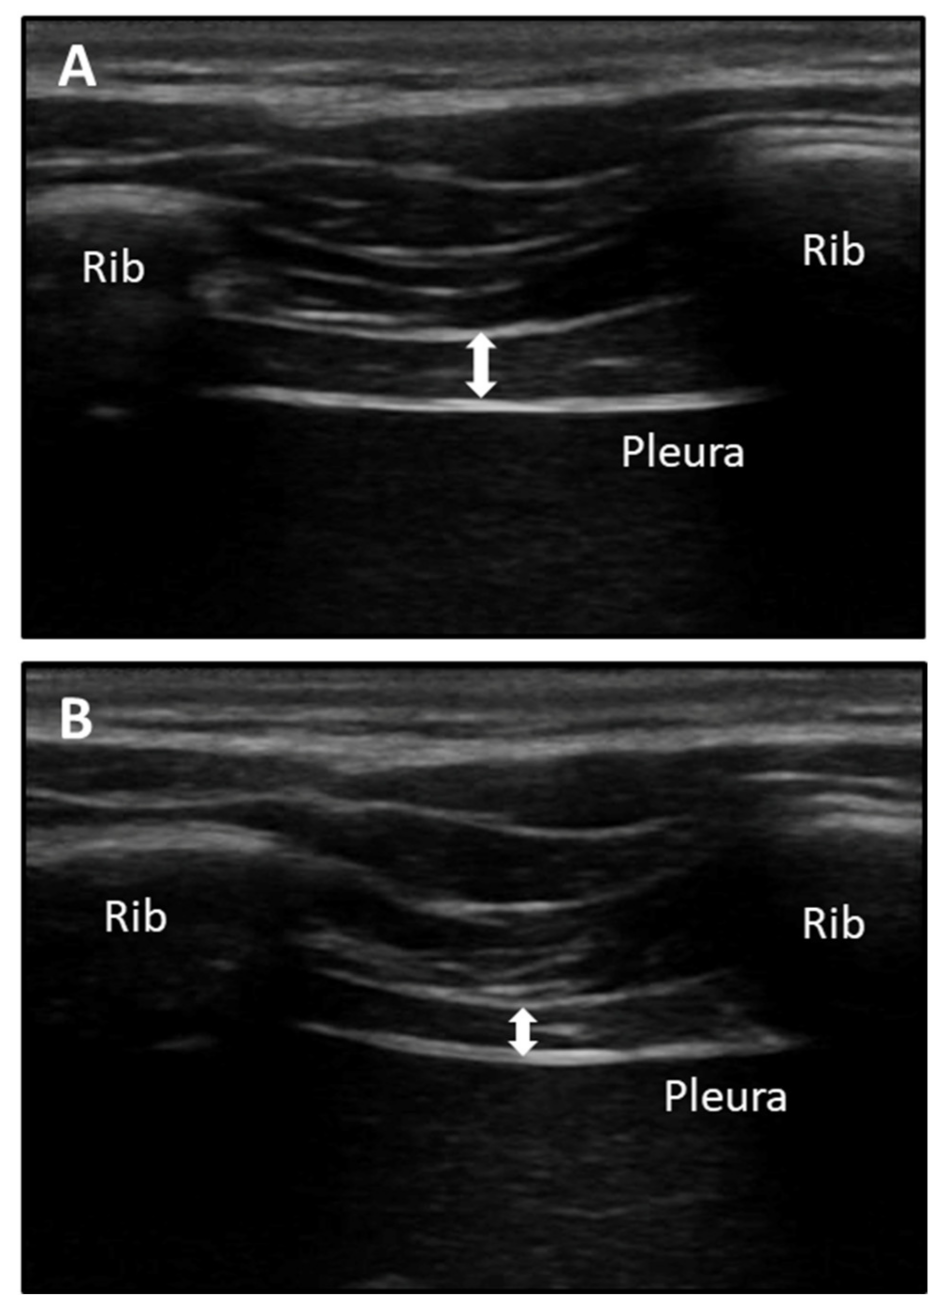

2.7. Ultrasound Measurements